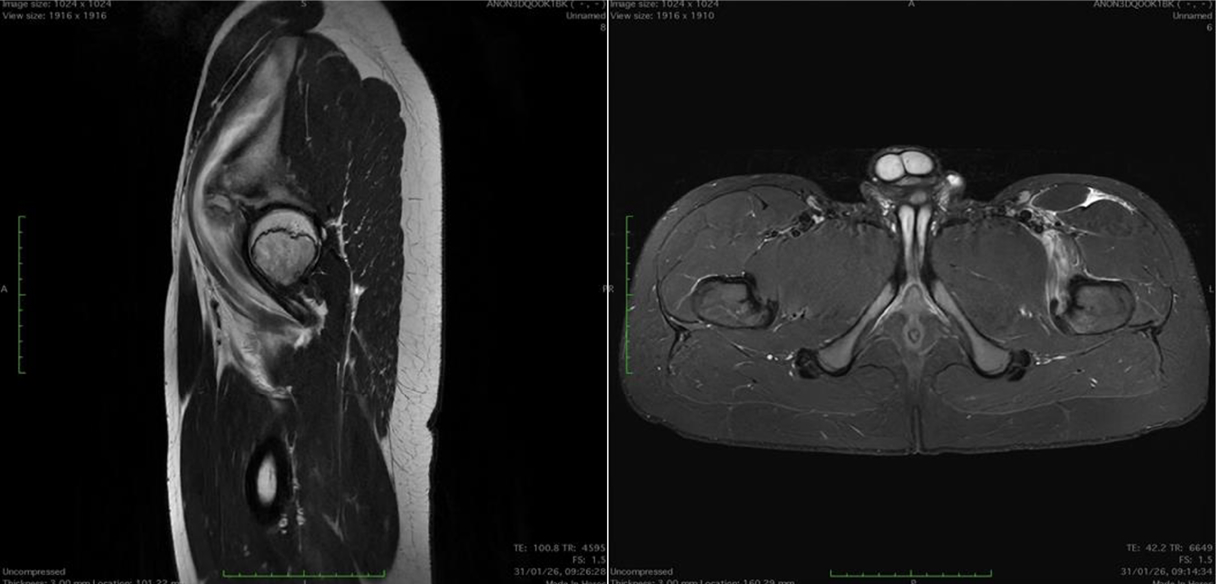

Fifty shades of grey

Caso condiviso da Marcello De Santis